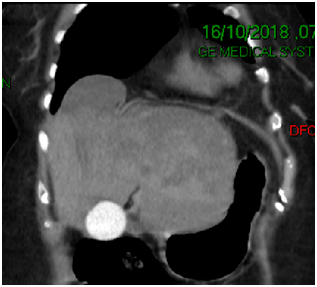

68-year-old female with presence of secondary hypothyroidism 8 years of evolution in treatment with levotiroxin, systemic hypertension 2 year of evolution treated with losartan, thyroidectomy 8 years ago, c-sections 243 and 38 years ago, the patient denies the use of alcohol or tobacco. Initiates with sudden transitive pain in epigastrium, vomiting several times, undergoing imaging and laboratory tests diagnosing pancreatitis its determined that the patient is in need of a ERCP, which is performed at a private institution, during the procedure the major duodenal papilla is identified anatomically normal but without bile output with multiple cannulation attempts (Figure 1), continuing with procedure applying contrast appreciating two gallstone suggesting images in distal choledocus which measures 9 mm in diameter (Figure 2) with a probable stenotic area in the distal portion, a wide sphincterotomy is performed with posterior passing of extraction balloon doing multiple sweeps obtaining two 7 mm gallstones due to said area of stenosisa 10 fix 10 cm stent is placed towards the right hepatic duct. After the procedure the patient presents moderate to intense pain in right hypochondrium alongside hypotension, administrating crystalloids and vital sing stabilization ordering CT scan where a sub capsular collection is visualized, varying heterogenicity from 600 to 20 HU, highly suggestive of a serohematic component with approximate size of 17 by 13.8 by 6.5 cm, with approximate volume of 820 cc (Figure 3) (Figure 4) with diagnosis of a probable subcapsular hematoma, with later presentation of acute kidney failure requiring temporary renal substitution therapy, once she was hemodynamically stable its moved to our unit to continue treatment, taking laboratory exams determining hyperbilirubinemia, due to conjugated bilirubin and elevated liver enzymes, deciding to do new CT scan where a 20% diminution of hematoma size is appreciated and adding pleural effusion to the findings deciding to give a conservative management, eight days later performing control ultrasound finding hematoma with a tendency to re absorption .

Figure 3 Coronal tomography showing the hepatic hematoma.